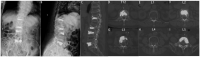

This study aimed to present a special case of treatment of a patient with multisegmental vertebral compression fracture, burst fracture, and sandwich vertebra and to review the literature on this condition. An 85 year-old female presented with severe low back pain but no radiating pain in the lower extremities. The patient was diagnosed with T12 and L5 vertebral compression fractures, fresh vertebral burst fractures in L2 and L3, and osteoporosis. The focus was on formulating a surgical treatment strategy. At the 12 month follow-up, no neurological deficits were observed, and the chosen surgical treatment approach yielded favorable clinical outcomes. A comprehensive literature review indicates that percutaneous kyphoplasty (PKP) can effectively alleviate pain and ensure safety in managing osteoporotic vertebral burst fractures. While complications remain a theoretical risk, they can be mitigated through meticulous assessment, careful surgical procedures, and appropriate preventive measures. PKP is an effective and safe treatment modality for osteoporotic vertebral burst fractures. Conservative management of sandwich vertebrae can yield positive clinical outcomes, but regular anti-osteoporosis treatment is necessary.